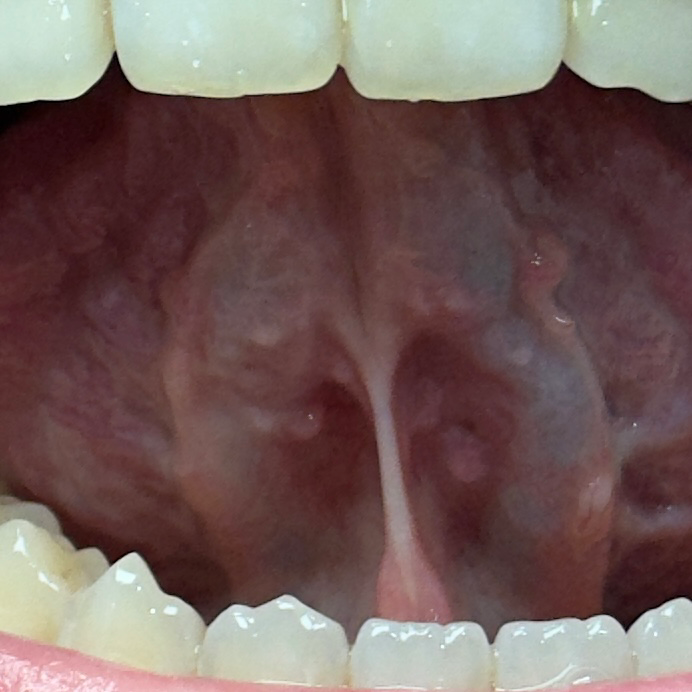

혀 아래 부분에 돌기?뾰루지?같은게 있어요

혀 아래 부분에 돌기나 뾰루지 같은게 많이 있어요.

• 2번 째 사진

특별히 병적인 상태로 보이지는 않습니다. 점차 모양이나 크기의 변화가 저명하다면 이비인후과나 구강전문의를 방문해보시기 바랍니다.